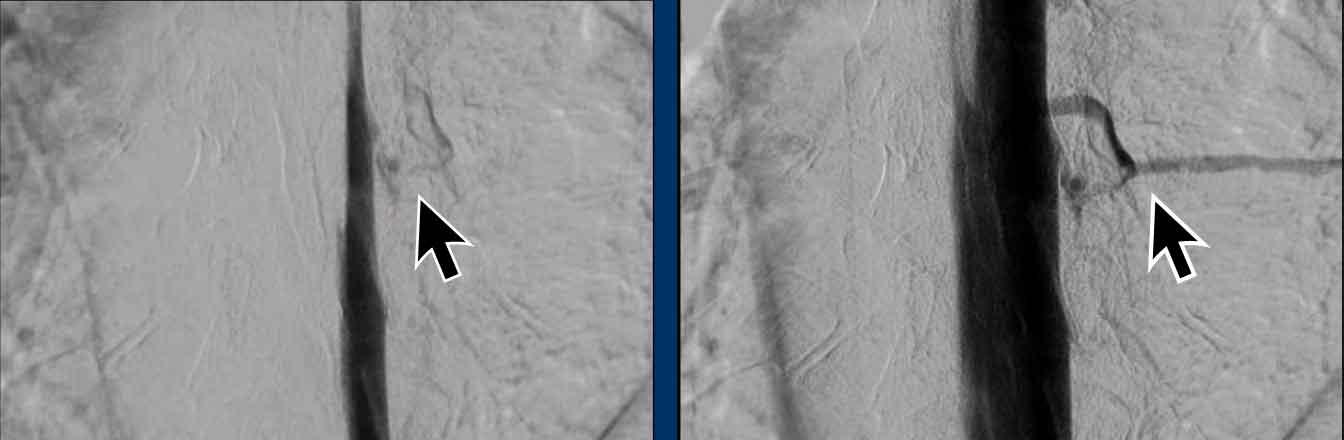

Cuối cùng, chụp tủy đồ xóa nền kỹ thuật số (digital subtraction myelography) được thực hiện (Courtesy René van den Berg).

Đầu tiên, tiến hành chọc dò thắt lưng.

Sau đó, bệnh nhân được đặt nằm nghiêng một bên và chụp ảnh với chùm tia nằm ngang trong khi thuốc cản quang được bơm vào và di chuyển theo hướng lên trên (xem video).

Khi bệnh nhân nằm nghiêng trái, không thấy bất thường nào.

Video này được ghi lại khi bệnh nhân nằm nghiêng phải.

Câu hỏi

Bạn có thấy rò dịch não tủy nào không?

Tiếp tục với các hình ảnh tiếp theo…

Ở mức ngực thấp, có hiện tượng rò thuốc cản quang qua một rò dịch não tủy – tĩnh mạch.

Hình ảnh

- Rò dịch não tủy – tĩnh mạch (mũi tên).

- Điều trị bằng phương pháp can thiệp nội mạch và thuyên tắc qua đường tĩnh mạch.

- Khối vật liệu thuyên tắc có thể nhìn thấy trên hình ảnh không xóa nền bên phải.